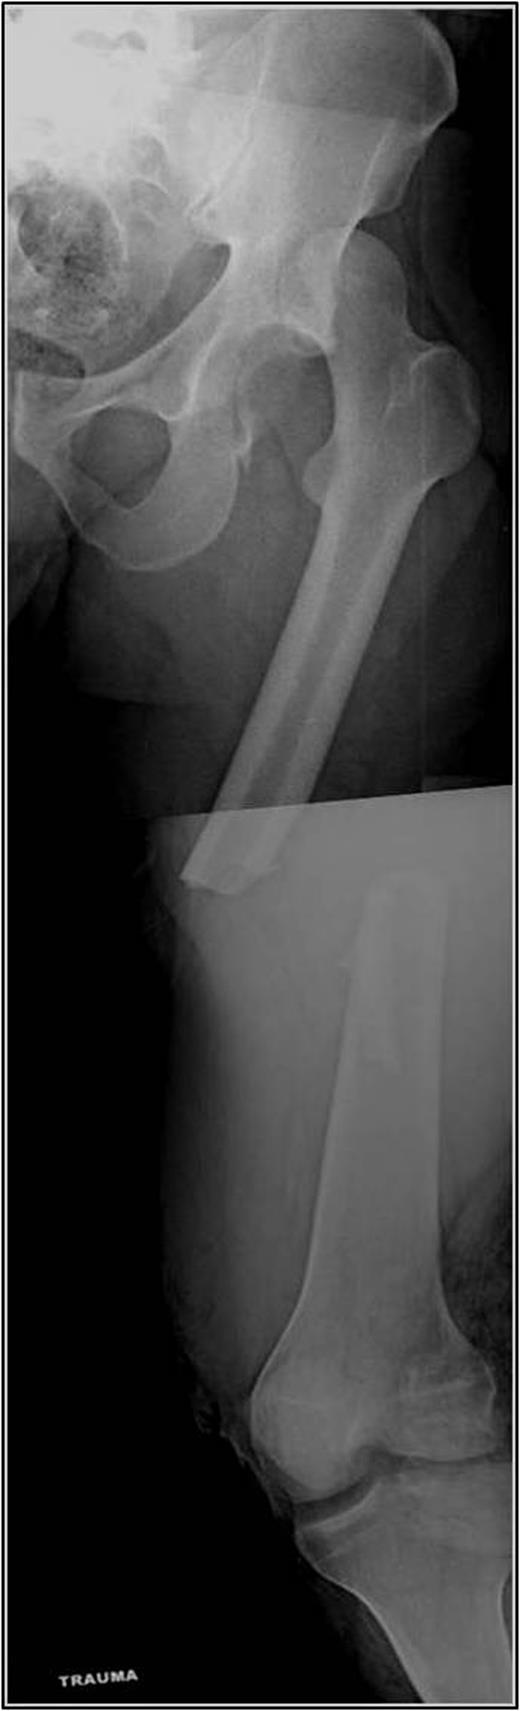

A 35-year-old male was involved in a high-speed urban dirt biking accident. The patient was stable with a GCS of 15 and was neurovascularly intact. His left knee exhibited a 10 × 20 cm medial traumatic arthrotomy and his thigh compartments were soft and compressible. Imaging revealed a left hip postero-superior dislocation, posterior wall acetabular fracture, ipsilateral transverse femoral diaphyseal fracture and an engaging hill-sachs-type lesion of the femoral head with the postero-superior acetabulum (Figs 1–3). Cefazolin, gentamicin and tetanus prophylaxis were administered along with a bedside washout of the traumatic arthrotomy. The patient was medically cleared for operative intervention as all blood work and further imaging were normal.

AP left femur of type B floating hip with associated hip dislocation. The medial knee soft tissue injury is also appreciated.